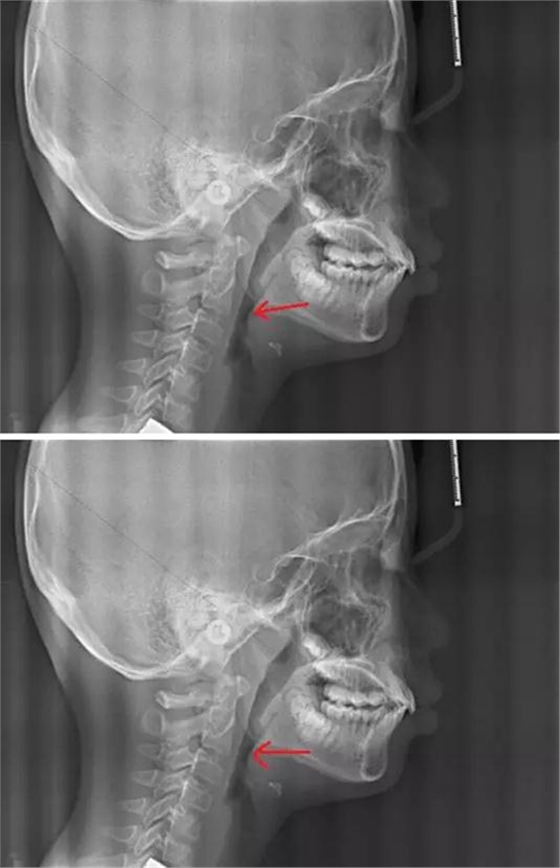

最后我們來對比一下正常的腺樣體和扁桃體的形態(tài)及位置,我們可以看到,正常的腺樣體和扁桃體在同一個位置形態(tài)的差異。